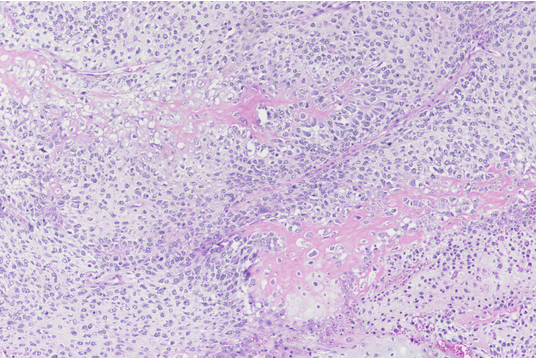

Gatto Maschio intero 13 anni. Cute orecchio. Carcinoma a cellule squamose (Ematossilina-Eosina x20).